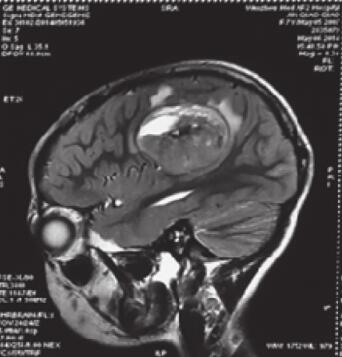

2014-7-22患者于放疗科入院治疗。查体:神清,对答切题,KPS 90,四肢肌力Ⅴ级,病理征阴性(图2)。

图2 术后头颅MRI(2014-7-22)显示病灶切除,术野局部可见条索样强化